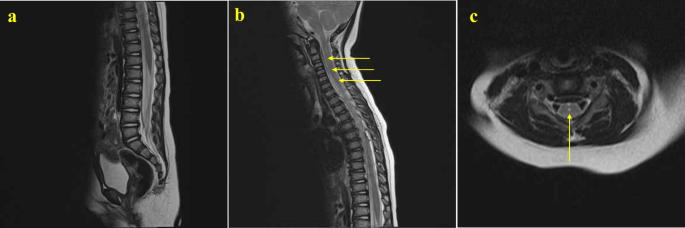

We present two cases with high-level spinal lesions. The first was a boy diagnosed with low-type ARM with an anocutaneous fistula, who underwent posterior sagittal anorectoplasty at three months. Preoperative LāS spine MRI revealed a lipoma in the spinal canal at the S1āS3 level, hemivertebrae at T10 and T11, and spina bifida at the lower sacrum. These findings resulted in a neurogenic bladder and left leg weakness with an unstable gait, requiring an extensive rehabilitation program. No spinal surgery was performed. After three years, due to claudication following long-distance walking, he underwent another MRI series. This whole spine MRI showed a tethered cord with lipoma extending from L4 to the sacral region, hemivertebrae at T10 and T11, and spina bifida consistent with the previous image. Additional findings included hydromyelia or syrinx extending from C5 to the conus medullaris and scoliosis of the TāL spine (Fig.Ā 2). Despite these findings, no surgery was required, and he continued with the rehabilitation program. The second patient, diagnosed with low-type ARM with an anoperineal fistula, underwent surgery at two months of age. Her WS MRI at 11 months showed normal findings in the lumbosacral region but hydromyelia extending over the C2āC7 spinal cord (Fig.Ā 3). She exhibited no neurological symptoms associated with the hydromyelia during outpatient follow-up, and no spinal surgery was performed.

Magnetic resonance imaging (MRI) of a girl having low-type anorectal malformation with an anoperineal fistula. Whole spine MRI at 11 months showed (a) normal findings in the lumbosacral region but (b,c) hydromyelia extending over the C2āC7 spinal cord (arrows).